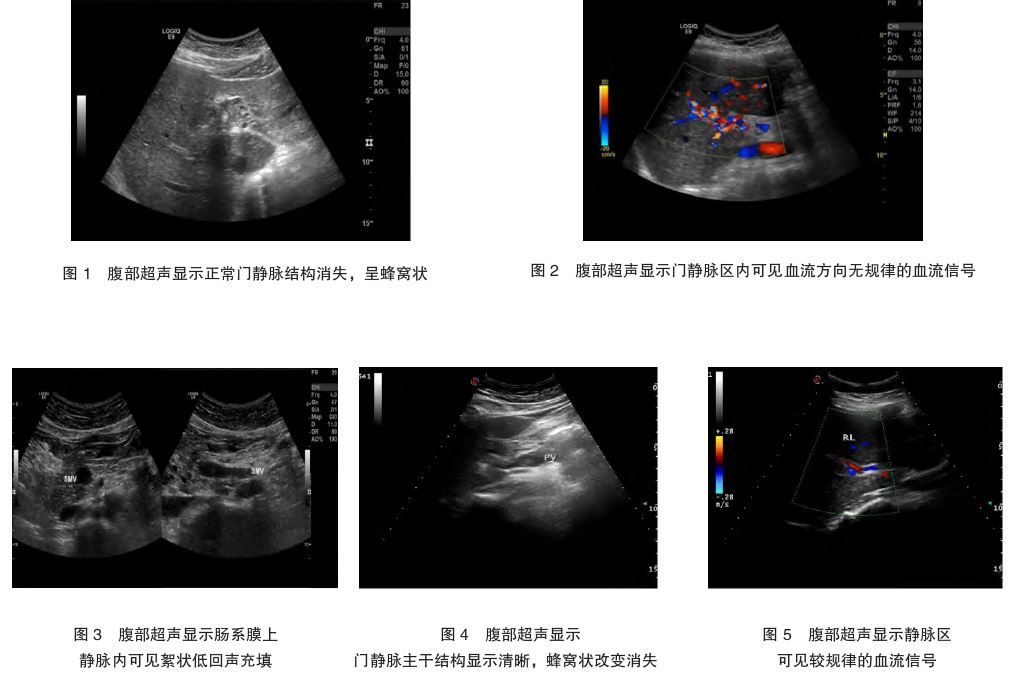

、抗核抗体、自身抗体谱、类风湿疾病等化验均阴性。腹部超声检查:CTPV(主干及右支),PVT形成(图1、2);胆囊结石

入院后予以间苯三酚

CTPV患者肝功能多正常,较少出现腹水、黄疸

症状,当门静脉压迫胆管时可出现黄疸。CTPV在二维超声中可表现为门静脉周围蜂窝状血管结构,门静脉管壁增厚、管腔变细或阻塞,管腔内出现中低回声。彩色多普勒观察门静脉及周围可见血流信号丰富、稀疏甚至无血流信号区域[7]。目前,门静脉血管造影是诊断CTPV的金标准,但其属于侵入性、有创性检查,不作为临床诊断首选。CT和磁共振分辨率较好,能更加清晰地显示CTPV的血管结构及有无血栓形成,三维动态增强磁共振血管造影

对门脉系统的显示更加直观,对临床诊断CTPV及PHT的严重程度和治疗效果评估具有重要价值[8]。但CT对于妊娠期患者不适用,磁共振费用较高。本例患者因腹痛入院,首选超声检查,发现CTPV伴PVT,及时明确病因有助于为下一步临床治疗提供依据。

胚胎移植术后并发CTPV较为少见,临床表现无特异性,虽然该病目前不属于妊娠禁忌证,但死亡率较高,仍需引起重视。CTPV在超声检查中具有特异性表现,有助于早期诊断,以及时采取抗凝治疗,降低死亡率。此外,临床针对此类孕妇还应监测凝血功能,定期复查腹部超声,必要时采取多学科会诊,结合孕妇具体情况调整治疗方案。